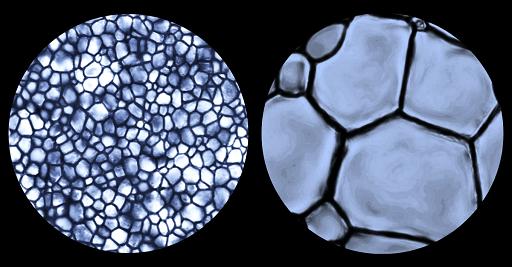

Small ice crystals are innocuous but large ice crystals damage cell membranes easily. These small crystals are like grains of sand on a Caribbean beach which are so small that they mould to your body and you can lay comfortably on the beach for an entire day. Now, let's say those grains of sand were replaced by gravel or pebbles. That's a lot less comfortable. Our cryopreservation technology prevents ice crystals from growing (and thus remain small) during freezing and thawing ensuring the survival of cells.